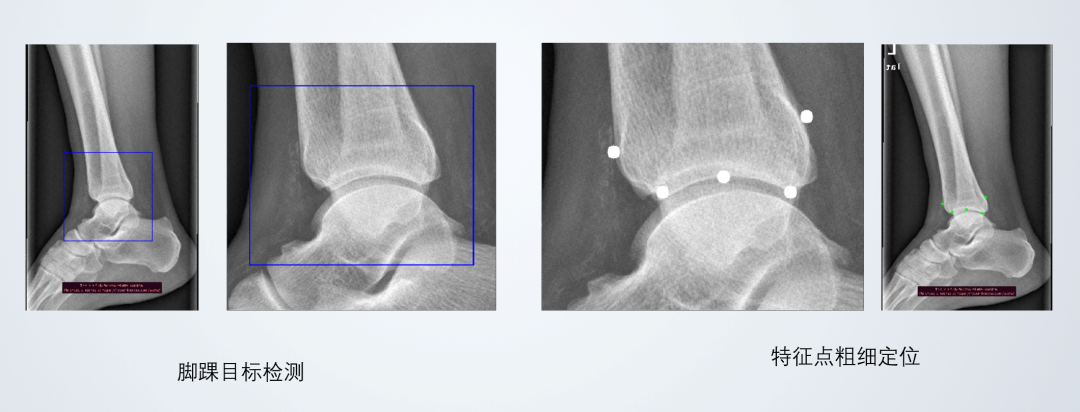

西安光影传感基于昇思MindSpore全场景AI框架,训练级联卷积神经网络,以逐步逼近的方式,预测图像的特征点位置,根据预测结果可用程序方便地换算出脚踝关节的相关尺寸参数,从而选择合适的踝关节假体。此项技术亦可用于人体其他关节形态学参数识别和假体选型。

(医学骨骼影像形态学参数自动识别与测量)

医学骨骼影像形态学参数自动识别与测量联合解决方案支持大批量数据处理,可实现短时间内处理大量数据,大大节省时间人力成本。同时该方案具备较高数据训练分割速度和准度,可有效保住数据稳定的精度。与此,该方案验证了神经网络用于人体测量的可行性,可以拓展到更广泛的医学测量领域,对接上下游,推进关节假体定制化。

(医学骨骼影像形态学参数自动识别与测量效果展示)